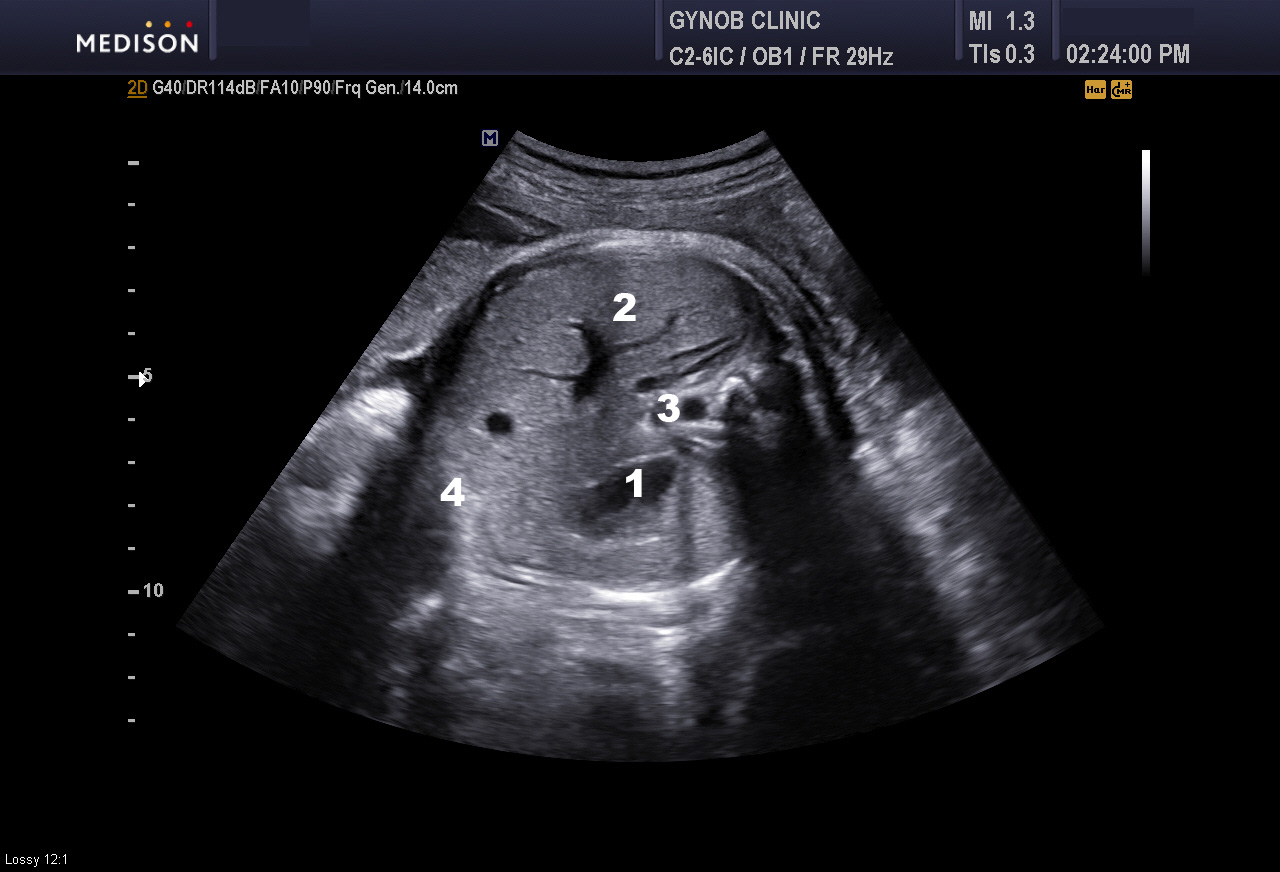

참고로 위의 사진은 저희 병원에서 찍은 사진으로 정상 복부 초음파의 소견입니다.

태아는 성인과 다르게 복부가 타원형이기보다 양수에 떠 있고 한 이유 등으로 거의 동그란 원형에 가깝습니다.

사진에 나타낸 숫자는 아래의 장기에 해당합니다.

1번: 위장

2번: 간

3번: 대동맥

4번: 복벽